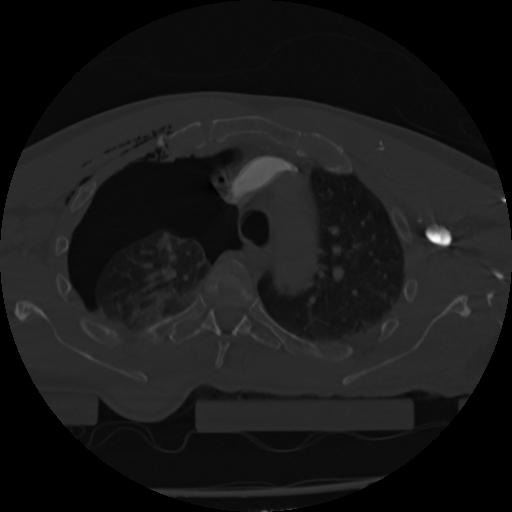

22 ANGIO,CE,Vol,0.5,ANGIO,,